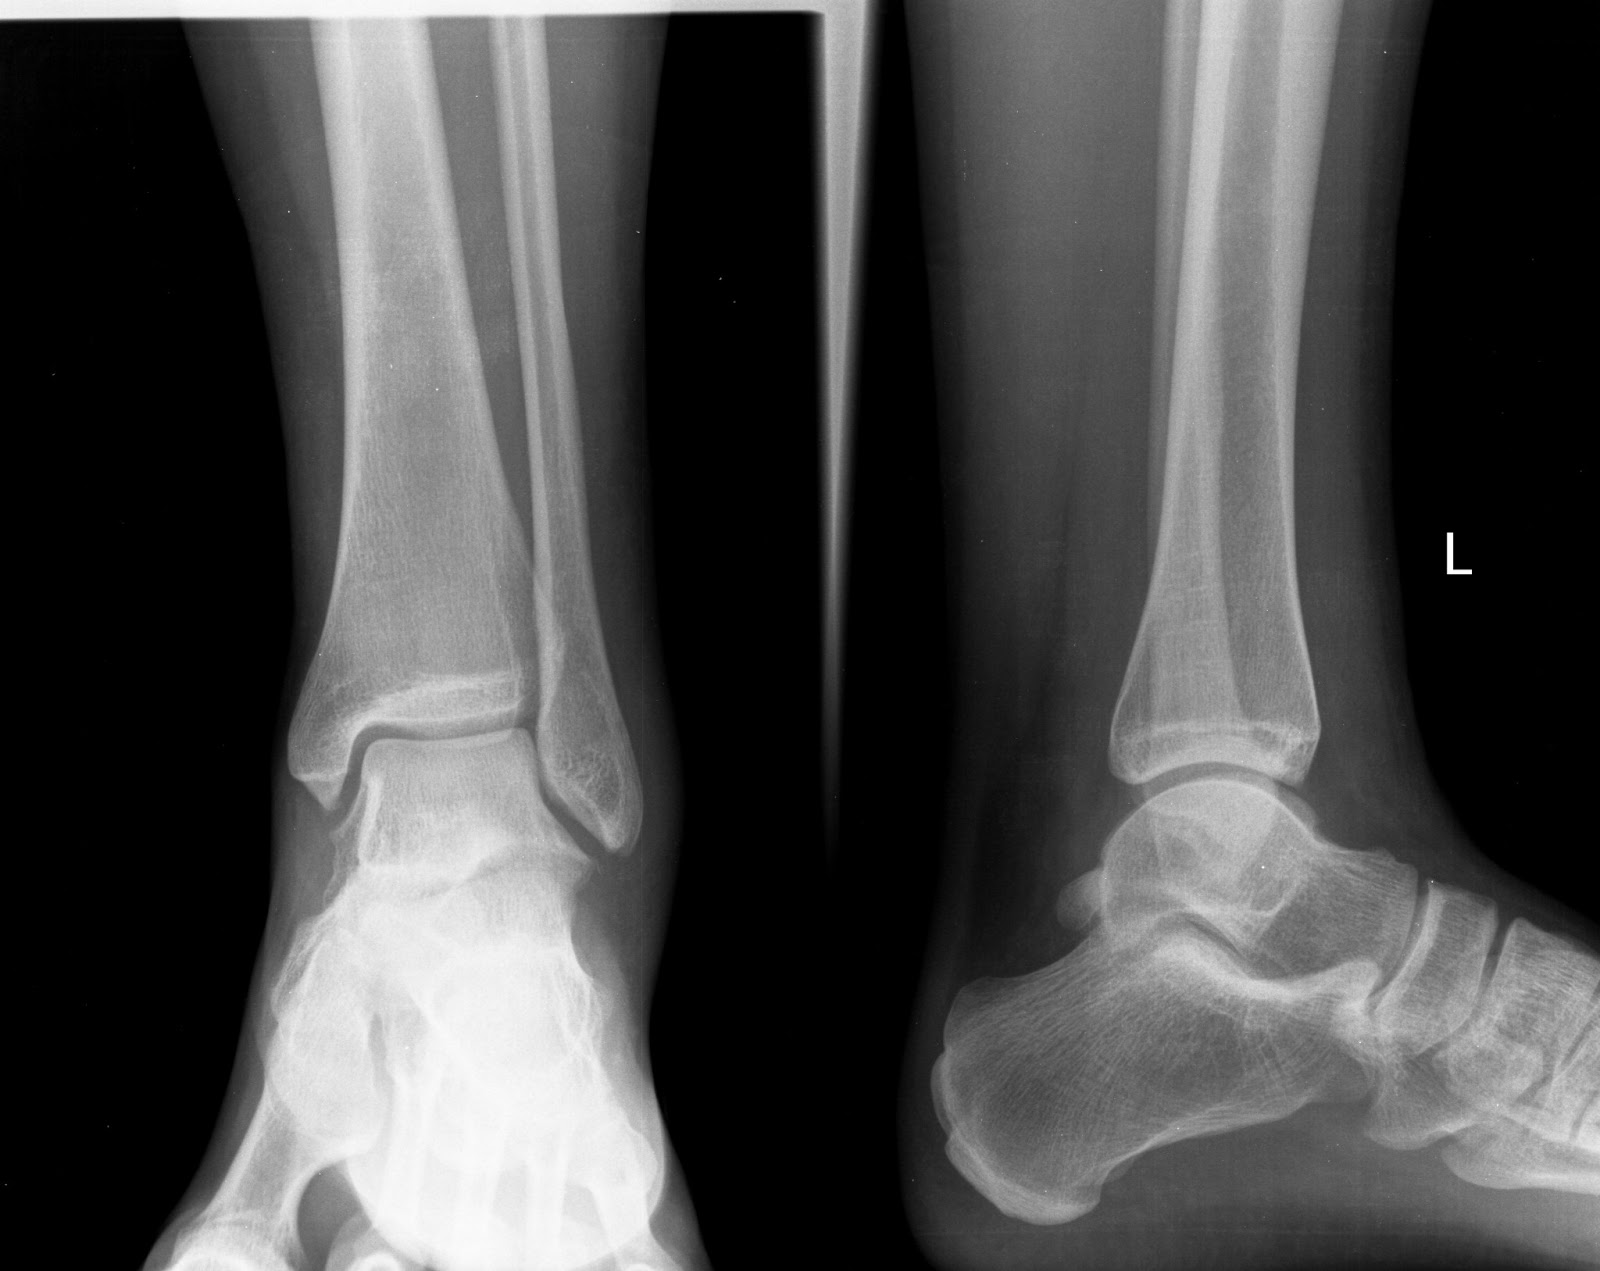

| LTFA: ant. talofibular lig., FL: fluid, AV: avulsion |

- Ligamentous injury